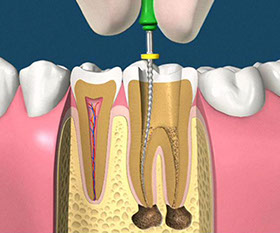

• asportazione della polpa e sagomatura dello spazio endodontico con strumenti meccanici (in nichel-titanio), con l'ausilio della detersione del canale radicolare (acqua ossigenata, ipoclorito di Sodio, calcio-chelanti)

• otturazione di tutto l'endodonto mediante materiali termoplastici (guttaperca) e cementi biocompatibili